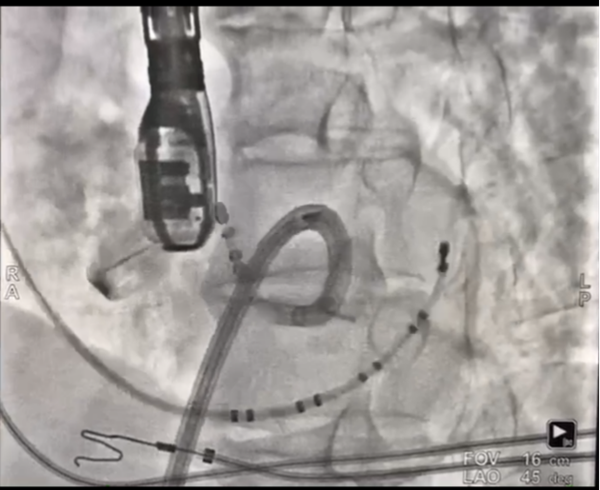

主动脉瓣下激动标测和射频消融

患者进入手术室麻醉后,室早消失,薛荣亮主任和李伟主任对麻醉药物精确滴定,既保证有稳定的室早出现,又保证患者的麻醉效果。超声室金鑫医师迅速实施食道超声插管。心内科郑强荪主任、王洪涛医师、郝广华医师和苏丹医师随即实施手术。首先穿刺股动脉,将消融导管逆行送入主动脉窦部位,在主动脉金属瓣上谨慎操作,行激动标测,未标记到室早最早激动点。考虑患者存在主动脉瓣金属瓣,消融导管不宜直接跨瓣膜操作,遂穿刺股静脉,在食道超声指导下行房间隔穿刺,将可调弯鞘管和消融导管依次送入左房、左室,以非同平面双弯角度最终把消融电极成功送入主动脉瓣下,标记到室早最早激动点。随着放电消融的“滴滴声”,10秒后,室早即刻终止。逐步增加功率,巩固消融后,室早未再出现,大家如释重负。术后持续心电监护显示,室早一个都没有出现,彻底解决了困扰患者多年的心悸问题。